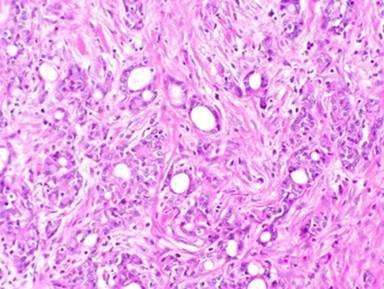

Due to concern for periampullary malignancy, the patient underwent a pancreaticoduodenectomy. Pathology revealed an ampullary adenocarcinoma with negative surgical margins and 1/9 positive lymph nodes (Figure1). He subsequently underwent 5 weeks of adjuvant chemoradiation with capecitabine and a total of 4500cGy of radiation therapy, followed by 4 months of adjuvant gemcitabine therapy alone. Following completion of adjuvant therapy, he was clinically well, with no evidence of recurrent disease.

Figure 1. High power view of the patient’s primary ampullary adenocarcinoma 21 months prior. The primary tumor is extremely similar histologically to the metastasis in the hydrocele sac. Compare to figure 4. (hematoxylin and eosin stained sections, 200X original magnification). |